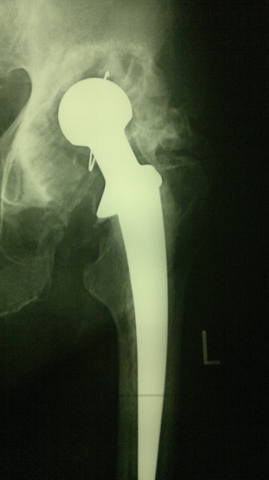

Здравствуйте, дорогие читатели нашего форума!<br /><br />Эндопротезирование при дегенеративно-дистрофических заболеваниях, а также травмах и их последствиях остается актуальным, бурно развивающимся направлением в современной ортопедии. С каждым годом в мире увеличивается число лиц нуждающихся в выполнении подобного рода операций. <br /><br />Замена собственного сустава искусственным позволяет огромной категории больных избавиться от хронического болевого синдрома, восстановить объем движений и функцию пораженного сустава, вернуться к своей профессиональной деятельности. <br /><br />В то же время известно, что каждый эндопротез имеет свой определенный "срок службы", длительность которого зависит от целого ряда обстоятельств. С одной стороны  это качество материалов, применяемых для изготовления имплантатов, с другой - особенности пациента и т.д.<br /><br />С увеличением пула пациентов, которым была выполнена первичная операция, возрастает нуждаемость  в так называемом "ревизионном эндопротезировании". Актуальность темы обусловлена тем, что хирург сталкивается при ревизии с уже не обычной ситуацией, в которой анатомические ориентиры часто бывают разрушены.<br /><br />В тему предлагаю выкладывать реальные клинические случаи и примеры ситуаций, с которыми сталкивается ортопед при ревизионном эндопротезировании.<br /><br />Начну с двух случаев. <br /><br />Первый: женщина, 80 лет, срок службы тотального цементного эндопротеза тазобедренного сустава 19 лет.<br /><br /> <br /><br /> <br /><br />Второй:<br /><br />женщина, 64 года, тотальный безцементный эндопротез тазобедренного сустава, срок службы 15 лет:<br /><br /> <br /><br />Третий:<br /><br />женщина, 60 лет, тотальный цементный протез тазобедренного сустава, срок службы 10 лет:<br /><br />